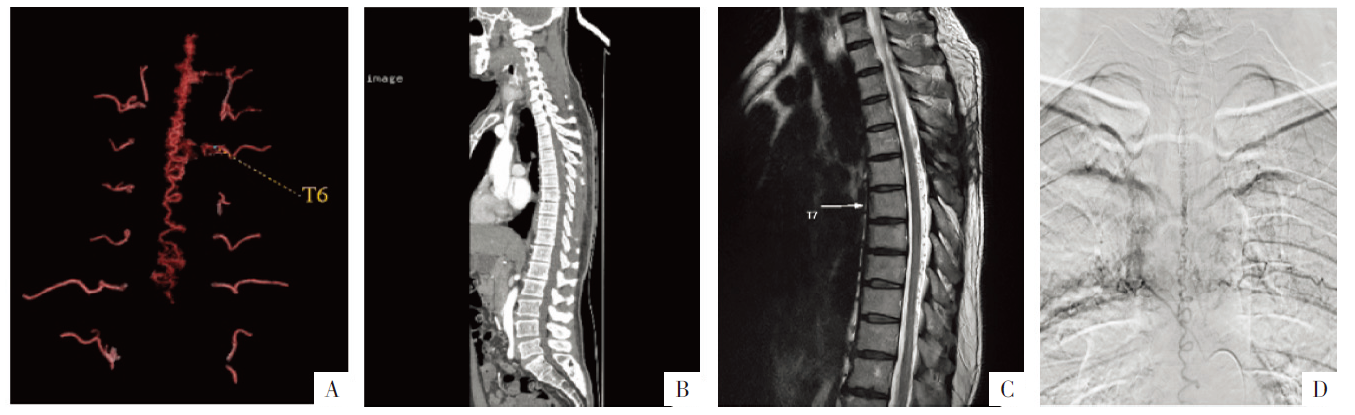

图1

病人男,49岁,1年前出现双下肢麻木并伴下肢力量减弱,4个月前症状加重,诊断为脊髓血管畸形。A图,CTA VR重组影像显示胸段椎管内可见迂曲畸形血管影;B图,CT矢状面重组影像显示胸段椎管内可见迂曲畸形血管影;C图,MRI平扫T

2

WI显示胸段椎管内可见留空血管影(箭);D图,DSA影像显示胸段椎管内畸形血管影。